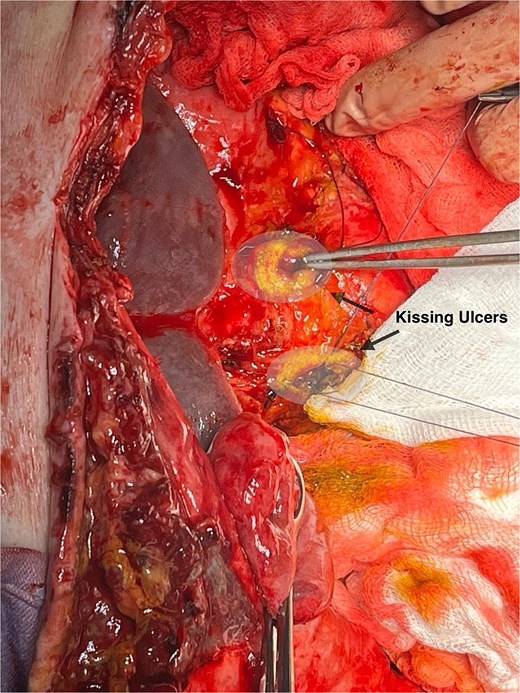

In this patient, median laparotomy was enabled by inverted-L incision, exposing a kissing ulcer during abdominal exploration (Fig. 1). Total mobilisation of ascending colon and caecum (Cattel-Braasch manoeuvre) and a complete Kocher manoeuvre were performed (Fig. 2). Cholecystectomy was also done with retention, thus serving for upper liver traction (Fig. 2). Once an enterostat was positioned just distal to the posterior peptic ulcer (Fig. 3a), a catheter was inserted through cystic duct to radiographically localise papilla of Vater during surgery. We injected contrast medium through the biliary catheter (with enterostat closed) to visualise the second and third parts of duodenum and confirm integrity of the papilla (Fig. 3b).

Anterior and posterior duodenal ulcers (arrows), each surrounded by yellow rim.